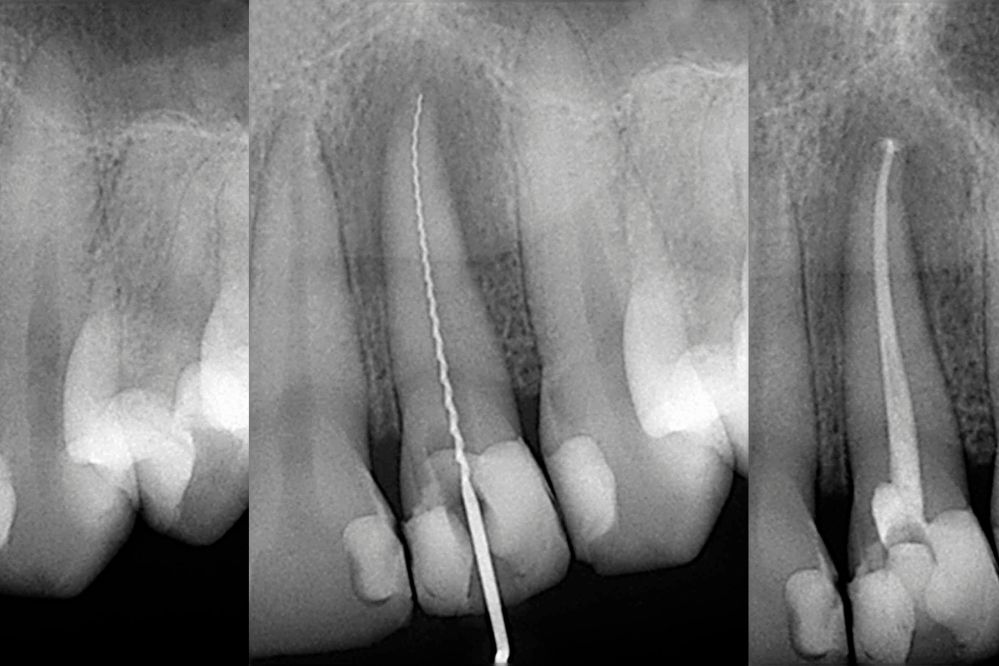

Nos enfocamos en una atención integral de tu tratamiento, por ello contamos con especialistas en Periodoncia (para atender correctamente tus encías) Endodoncia (tratamientos de conductos) Ortodoncia (para alinear tus dientes).